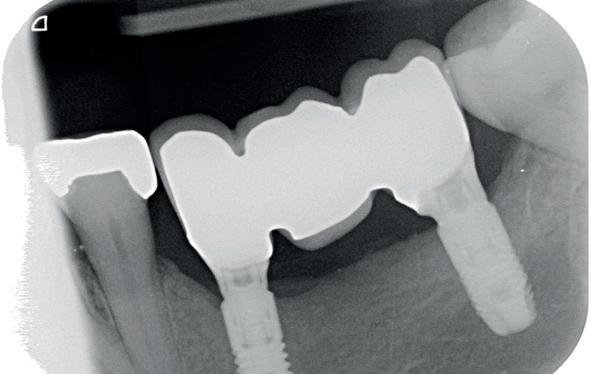

Bij klinisch en röntgenologisch onderzoek viel echter op dat radix van de 12 en 22 een convergerende (de radices staan dan naar mesiaal en naar elkaar toe) in plaats van divergerende (radices staan dan van elkaar af) stand had. Door deze convergerende stand van de radices was er in mesio-distale zin geen ruimte voor twee implantaten ter plaatse van de 11 en 21. Er werd daarom besloten, in tegenzin

1. Retainer met twee frontelementen

2. OPT radices 12 en 22 convergeren

4. OPT radices 12 en 22 divergeren na orthodontische behandeling

van de patiënt, om eerst weer vaste apparatuur terug te plaatsen om de radices in een divergerende stand te plaatsen. Gelukkig verliep deze behandeling voorspoedig. (afbeelding 2 -4). Het volgende behandelplan werd gemaakt: